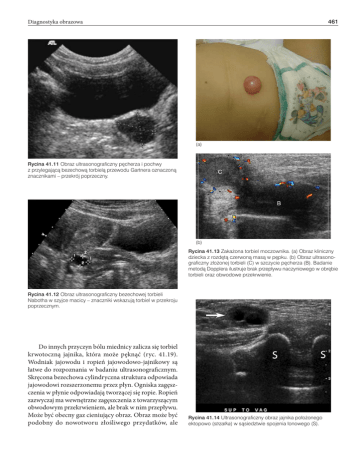

Rycina 41.13 Zakażona torbiel moczownika. (a) Obraz kliniczny

dziecka z rozdętą czerwoną masą w pępku. (b) Obraz ultrasonograficzny złożonej torbieli (C) w szczycie pęcherza (B). Badanie

metodą Dopplera ilustruje brak przepływu naczyniowego w obrębie

torbieli oraz obwodowe przekrwienie.